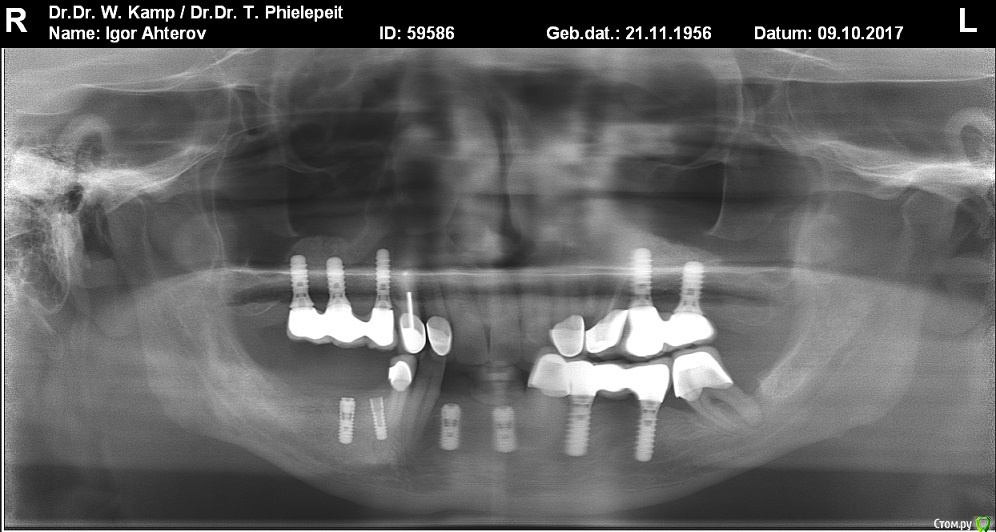

Antikwar Опубликовано 26 ноября, 2017 Поделиться Опубликовано 26 ноября, 2017 Доброго времени суток .Хотелось бы узнать компетентное мнение, врачей, З.техников. Вчера было установленно 2 моста (оксид циркония) на имплантанты перед низ и 2 коронки с боку правая сторона низ ..НА мой не опытный взгляд конструкция и сама работа не качественная и эстетика здесь полностью отсутствует. 1.Видно тело абатмента в обоих конструкциях. 2.Мост и коронки висят в воздухе и не прилегают к десне,как в первом так и во втором случае. Между десной и мостом (перед низ) проходит спичка. Вопрос, должен ли мой доктор переделать эту (на мой взгляд) не качественную работу ! Что вы мне посоветуете .... Заранее благодарю всех откликнувшихся. Ссылка на комментарий

Antikwar Опубликовано 26 ноября, 2017 Автор Поделиться Опубликовано 26 ноября, 2017 Так это и есть ответ на ваш вопрос,конечно по фото судить сложно,нужен рентген,но если это убыль костной ткани,то коронки могут быть досажены корректно,относительно импланта,проблема может быть в том,что уже кость ушла ниже уровня имплантата,а это коронкой не перекрыть никакк сожалению у меня есть только промежуточный ренге ренген но он неважного качества по пробую его отправить Ссылка на комментарий

AndyAndy Опубликовано 26 ноября, 2017 Поделиться Опубликовано 26 ноября, 2017 Довольно щекотливая тема, учитывая что вы вчера все же приняли работу, а сегодня уже хотите переделать. Общайтесь с вашим доктором, приходите к компромиссу. Касаемо имплантатов на н/ч, по снимку они в находятся в кости, видимых проблем с ними нет 2 Ссылка на комментарий

krokomot Опубликовано 27 ноября, 2017 Поделиться Опубликовано 27 ноября, 2017 целевая зона на снимке замылена, четкости нет, исходя из ваших фотографий проблемма не в коронках, а в позиции имплантатов - видна шейка имплантата, так быть не должно. нужны прицельные снимки этой области. Учитывая обстоятельства коронки изготовливаются исходя из положения имплантатов.и я так понимаю вас запротезировали из позиции то что есть, и вая явно нужно что-то делать. Ссылка на комментарий